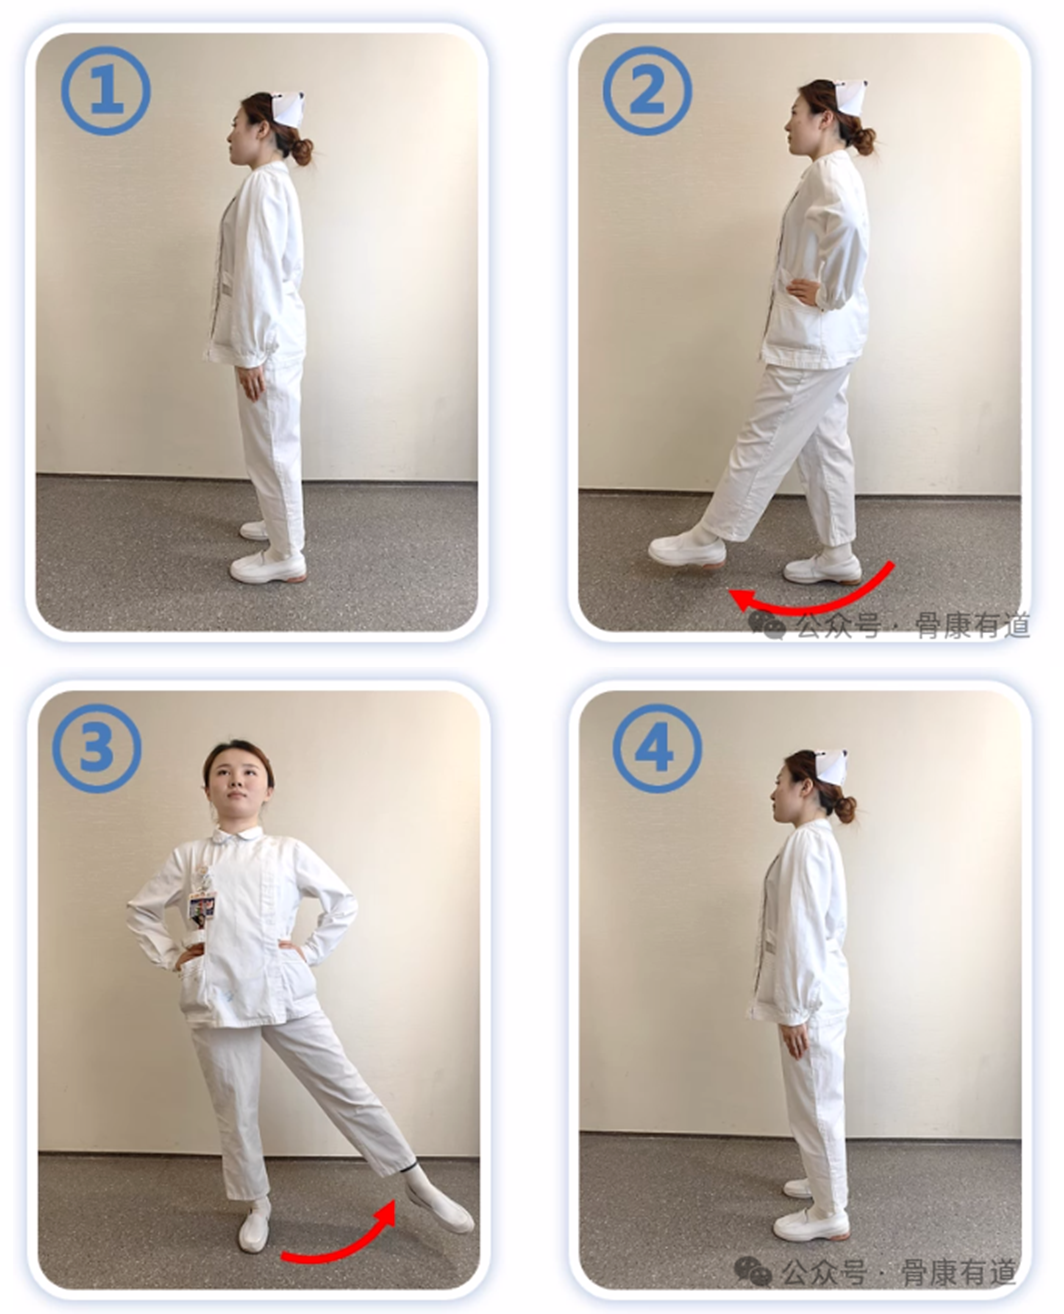

【训练方法】

①自然站立;

②左腿向前抬起30°;

③落下时脚掌不着地,再向左侧抬腿30°;

④最后还原落地。换右腿继续之前的动作。

①-②-③-④动作为一组,左右交替10次。可以单手扶椅背或护栏进行,前抬腿和侧抬腿时膝盖尽量伸直不要弯曲。